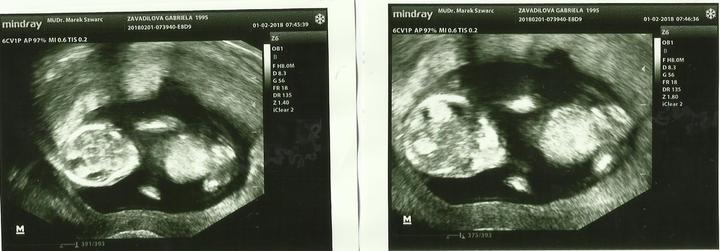

před nějakou dobou jsem vám zde psala že mám PCOS ( polycistycký sindrom).

Nemohla jsem rok a něco otěhotnět, jezdila jsem na různé vyšetření do Ostravského Gyncentra kde mi oznámili že nemohu mít děti na 98% + ani umělé oplodnění.

Měla jsem tudiž jen 2 % šance na otěhotnění 🙂

A ty 2% procenta asi byly dobré, jelikož jsem sice teprve ve 14 tt, ale i tak je to super pocit, jsme zdraví, silní, jen pohaví ještě nevíme.